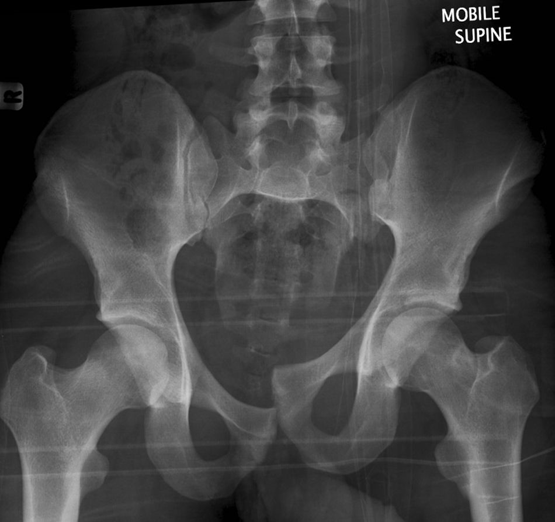

(1)Malgaigne 骨折

指垂直不稳定骨盆骨折,骨折累及双侧耻骨支、骶髂关节或者骶骨。

(6)Straddle 骨折

双侧耻骨上下支骨折。

(7)Walther 骨折

经过耻骨支并延伸到骶髂关节的髋臼骨折。髋臼的内侧面向内移位。